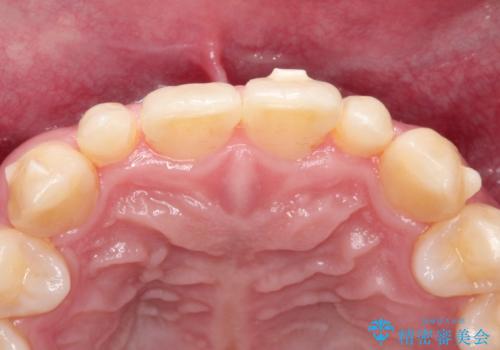

- 当院で矯正治療を行っており、上の前から2番目の歯の形も気になるので治したいと希望がありました。

矮小歯といわれる通常よりも小さい歯であったので、こちらにオールセラミッククラウンを装着して自然な歯の形にすることにしました。

上の前から2番目の歯を少量削らなければならないデメリットはありますが、クラウンの装着により自然な形へすることができました。